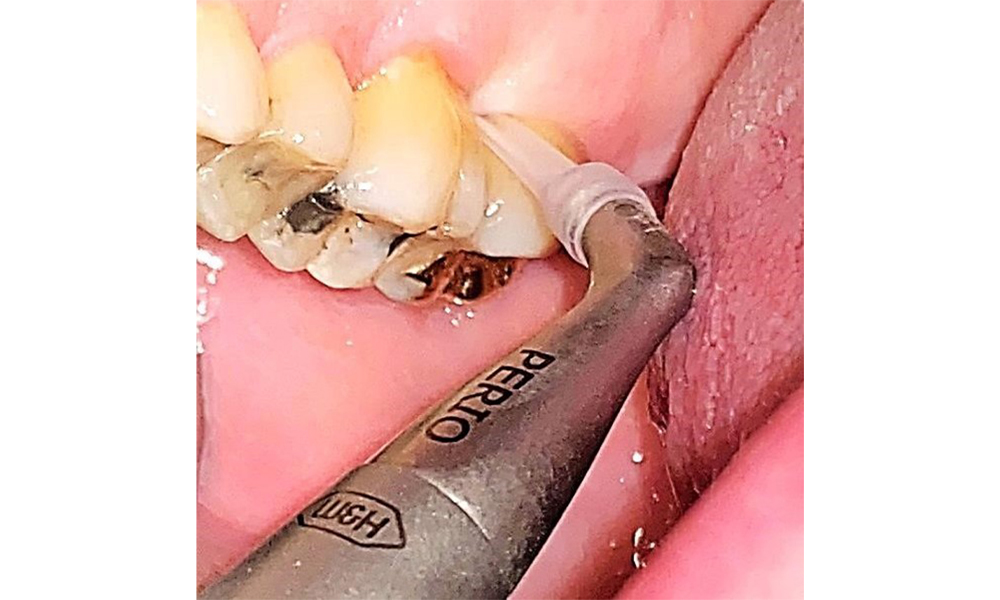

There are no limitations regarding the choice of instrumentation methods. Regular supragingival and subgingival instrumentation is essential to prevent disease progression due to the pre-existing periodontitis and high risk of recurrence. There are no limitations placed on the selection of instruments for mechanical biofilm removal from a general medical perspective, and removal should be performed as needed. Hard and mineralized plaque, such as calculus and concretions, should be removed using manual instruments or sonic/ultrasonic scalers (Fig. 9) (8, 9).

Supragingival and subgingival biofilm removal is indispensable for maintaining the stability of the periodontal condition. Air polishing using low-abrasive powder is suitable for this purpose. Periodontal pockets and exposed root surfaces must be cleaned with low-abrasion powders. The use of a flexible parotip is recommended for patients with increased probing depths (deeper than 5 mm) (Fig. 10). (9)

Pocket depths of up to 5 mm can also be managed using a conventional attachment (9). The use of an air polisher with a low-abrasive powder is also recommended for restoration margins, interdental areas and fissures. Rotary polishing (Fig. 11) gently smooths the tooth surfaces, which in turn supports the optimal end to prophylactic dental appointments and reduces bacterial re-adhesion (10).